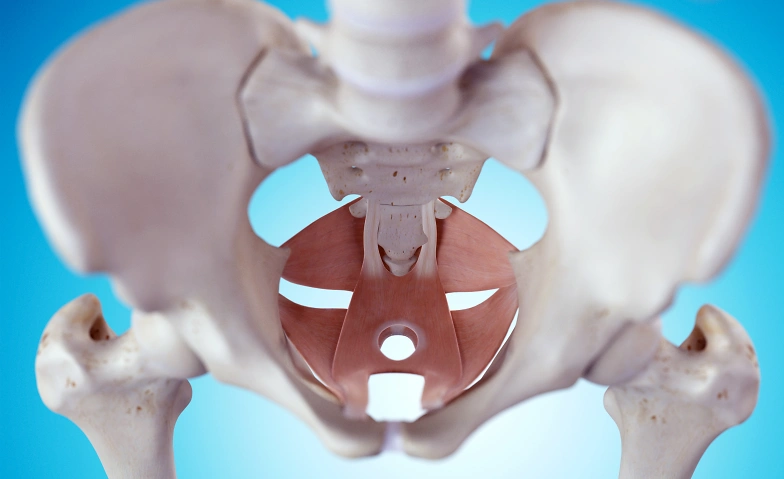

Der Beckenboden spielt eine zentrale Rolle für Haltung, Stabilität, Atmung, Kontinenz, Sexualität und Rückengesundheit – und wird dennoch oft vernachlässigt oder missverstanden.

Was ist der Beckenboden – und warum ist er so entscheidend?

Zusammenhang zwischen Beckenboden, Rücken, Atmung & Organen